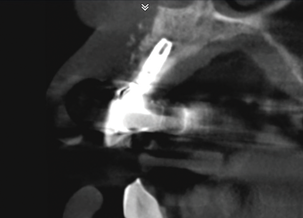

In this case, a dental implant that had been placed 10 years prior was functional, stable, and esthetically acceptable to the patient. However, a significant fistula was present on the facial-apical aspect of the ridge in the maxillary lateral incisor area. This area was painfully sensitive to touch and demonstrated purulence when squeezed. To evaluate the lesion, first, a conventional digital radiograph was acquired, which revealed an apical radiolucency at the apex of the implant (Figure 1). Further analysis using cone-beam computed tomography (CBCT) demonstrated a fistula from that site to the oral environment (Figure 2). Treatment options were discussed, including removal of the implant, followed by grafting, a healing period, and replacement of the implant and implant-retained crown. If this option was selected, a transitional appliance would need to be created. Another option was to attempt to salvage the implant and implant crown by treating the infection and grafting the site to create a new boney wall and eliminate the fistula. Ultimately, the patient accepted this option to attempt to salvage the fixture and crown.

Peri-implantitis was not the culprit behind the creation of this infected site; the lesion developed as a result of the position of the implant. Although the implant was initially stable upon placement, it was angled such that its apex had penetrated through the facial plate of bone. Without a sagittal CBCT analysis or a releasing flap performed to evaluate the initial placement, the surgeon could easily miss this. Regardless, the circumstances warranted evaluation of the apical aspect of the implant to attempt to salvage it.

(2.) Preoperative CBCT analysis demonstrating a fistula from the site of the radiolucency to the oral environment.

Figure 2